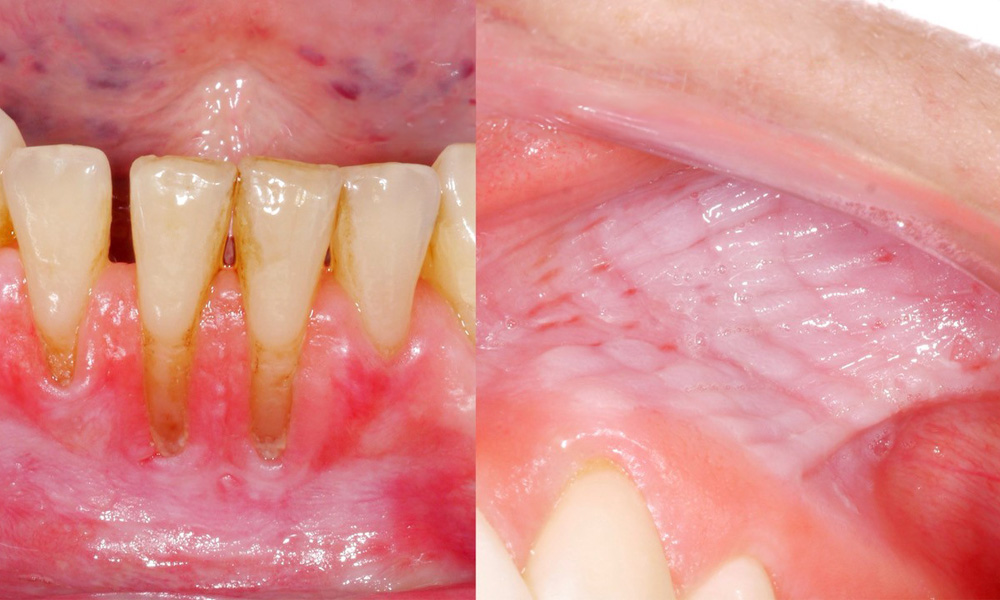

Клиничното изследване показа, че редовната консумация на снус може да има следните ефекти върху лигавицата на устната кухина:

- Приблизително 80% от изследваните лица, които са консумирали снус ежедневно, са показали лезии на лигавицата, предизвикани от него.

- Приблизително 20% от изследваните лица, които са консумирали снус ежедневно, са имали индуцирана гингивална рецесия.